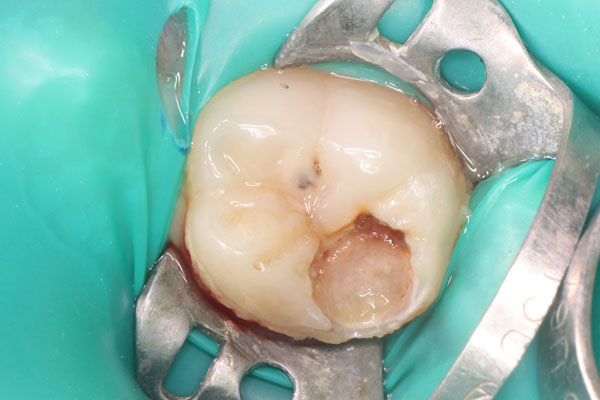

Примеры лечения зубов

Лечение кариеса

Лечение под микроскопом

Лечение кариеса под микроскопом (стоимость без учета снимка и анестезии)